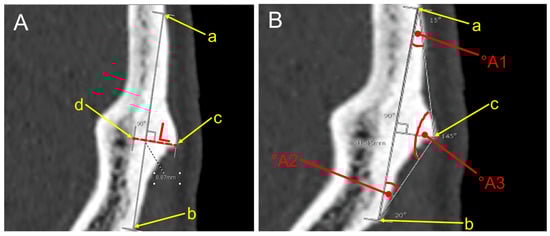

2.5. Morphometric Measurements

| Age Range (Years) | Morphometrics and Angles of EOP Type II (Means ± S.D.) | |||||||

|---|---|---|---|---|---|---|---|---|

| Female | Male | |||||||

| L (mm) | A1 (°A) | A2 (°A) | A3 (°A) | L (mm) | A1 (°A) | A2 (°A) | A3 (°A) | |

| 18–30 (n, 185) | 5.8 ± 0.2 | 19.6 ± 0.7 | 19.9 ± 0.8 | 140.5 ± 0.9 | 7 ± 0.2 | 23.5 ± 0.9 | 23.5 ± 1.1 | 133 ± 1.3 |

| 31–40 (n, 53) | 6.1 ± 0.5 | 18.3 ± 1 | 23.9 ± 5.4 | 137.89 ± 5.8 | 7.2 ± 0.4 | 25.3 ± 1.2 | 21.7 ± 1.1 | 132.9 ± 1.6 |

| 41–50 (n, 78) | 5.7 ± 0.5 | 18.2 ± 1.3 | 20.1 ± 2.4 | 141.7 ± 2.5 | 7.6 ± 0.5 | 23.8 ± 1.4 | 23.4 ± 1.4 | 132.8 ± 1.9 |

| 51–60 (n, 93) | 5.3 ± 0.2 | 18.1 ± 1.1 | 20.1 ± 1 | 141.8 ± 1.1 | 7 ± 0.4 | 23.5 ± 1.3 | 23.1 ± 1.2 | 133.4 ± 1.6 |

| >60 (n, 341) | 5.6 ± 0.2 | 19.4 ± 0.7 | 19.2 ± 0.5 | 141.4 ± 0.8 | 7 ± 0.2 | 22.8 ± 0.8 | 21.8 ± 0.7 | 135.4 ± 1 |

| Genders | Morphometry of EOP: Type II (Crest) | |||

|---|---|---|---|---|

| Length (L) of EOP (mm) | Angles of EOP (°A) | |||

| °A1 | °A2 | °A3 | ||

| Female | ||||

| Mean ± SD | 5.6 ± 0.1 | 19.2 ± 0.5 | 19.7 ± 0.4 | 141.2 ± 0.6 |

| Median | 5.6 | 18.5 | 19 | 141.8 |

| Min–Max | 1.7–11.5 | 8.3–72 | 7.8–45.5 | 92.5–157 |

| Male | ||||

| Mean ± SD | 7.1 ± 0.1 | 23.5 ± 0.5 | 22.6 ± 0.5 | 133.8 ± 0.6 |

| Median | 6.7 | 22.5 | 21.8 | 135.1 |

| Min–Max | 3.2–14.1 | 8.8–50.5 | 7.5–48.3 | 100–154.8 |

| p-value | <0.001 a | <0.001 a | <0.001 a | <0.001 a |